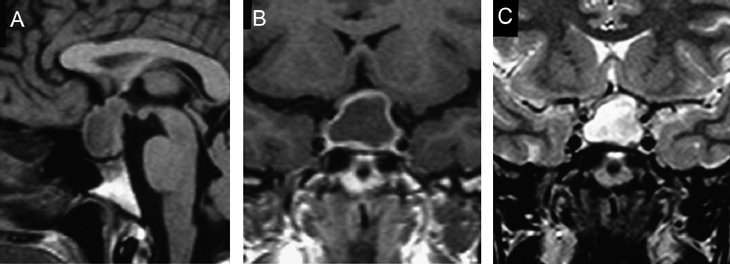

A diferencia de la tomografia computada, que emplea tubos de rayos X, la RM no utiliza radiaciones ionizantes, lo que es una ventaja a considerar en los pacientes pediátricos y en las mujeres embarazadas. La RM tiene una excelente resolución espacial y de tejidos blandos; por ejemplo permite precisar la presencia o ausencia de la neurohipófisis, lo que no es posible con la Tomografia Computada5-7. Con la TAC, con o sin medio de contraste yodado, es posible detectar microadenomas y macroadenomas pituitarios (Figuras 1A y 1B); sin embargo, en los macroadenomas puede ser difícil distinguir las relaciones del tumor con el quiasma óptico, o definir la invasión del seno cavernoso. Además, los artefactos producidos por amalgamas dentales deterioran las imágenes y la dificultad para lograr posiciones cómodas para los pacientes, con el fin de obtener cortes coronales directos, limitan la utilidad de la TAC.

En los tumores grandes (macroadenomas) la TAC puede entregar información diagnóstica adecuada, pero no supera la definición que se logra con equipos de RM superconductores (Figuras 2 A y 2B).

Figura 1A y B. TAC con contraste yodado, corte coronal, muestra un microadenoma lateralizado a izquierda (punta de flecha). Control a los 2 años. TAC con contraste yodado, corte coronal, demuestra aumento de volumen del microadenoma, lo que es infrecuente de observar en clínica (punta de flecha).

Figura 2A y B. Cortes sagitales de RM y TAC. Adenoma pituitario con invasión del esfenoides y del clivus (puntas de flecha). Es posible demostrar las estructuras óseas en RM con similar precisión que la TAC.